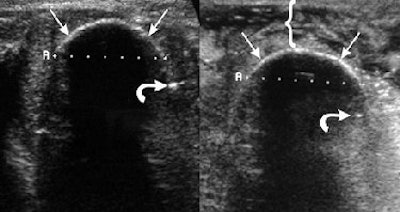

![]() |

| Same patient as above. At three minutes, note the thickened skin distance (bracket) due to interval saline injection. Transverse view of a large unusually shaped (i.e., discoid, not cylindrical) fibroadenoma with cryoprobes (straight arrows) in place (top) and growing ice at one minute (bottom). The thermocouple (curved arrow) is about to be engulfed in ice. The ice ball subsequently fused to create a smooth discoid shape, which was only possible with the probes placed less than 1.5 cm apart and approximately 1 cm from the fibroadenoma margin. Figure 1a,c,d. Littrup PJ, Freeman-Gibb L, Andea A, et al. "Cryotherapy for breast fibroadenomas," Radiology 2005; 234(1):63-72. |